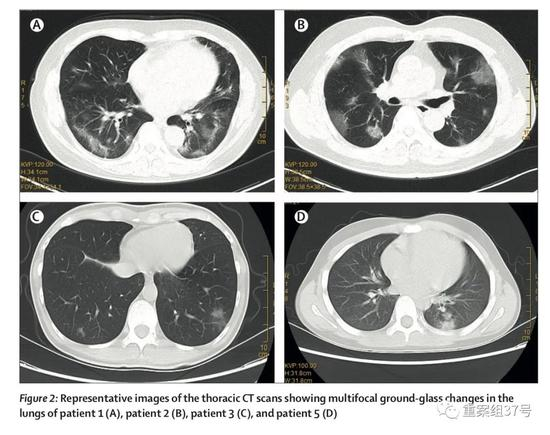

《柳叶刀》1月24日在线发表的一篇家庭聚集性病例研究论文中,香港大学李嘉诚医学院微生物学系、香港大学深圳医院临床微生物及感染控制科研究人员详细分析了上述深圳病例。在前往武汉的6名家属中,有5人被确认感染了新冠病毒。在武汉期间,这6名家庭成员都没有接触过动物,也没有去过包括华南海鲜市场在内的市场。但有2人去过武汉一家医院,探望因高热性肺炎住院的亲属。

▲有武汉旅行史的返深圳家庭中,多名家庭成员呈现肺部多发磨玻璃样改变,其中10岁的患者为无症状感染者。论文截图

一家人返回深圳后,女儿、女婿及孩子和亲家母住在一起。1月8日,亲家母出现背痛、全身无力等症状,在当地一医院接受头孢克洛治疗后无好转,并出现发烧、干咳等症状,于1月11日再次就诊。而她在过去14天内并未去过武汉或深圳市场,后确诊新冠肺炎。

论文分析道,存在几种传播可能性。其中最可能的情况是,在武汉某医院探望亲属时未戴口罩的孩子外婆被感染,一家人返回深圳后将病毒传染给孩子奶奶。“研究表明,这种新型冠状病毒可能在家庭、医院存在人传人现象,并可能在城市间传播,因此在流行早期阶段就应警惕,采取措施加以控制。”

值得注意的是,这起家庭聚集性病例中,还有一例无症状感染者(10岁)。上述论文提出,尽早隔离病人、追踪和隔离接触者至关重要,因为如10岁患者所示,可能存在无症状感染。